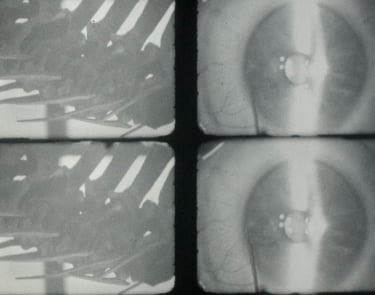

The intrusion in the physical and material body, articulated around three instructions.

It represents a progression in the search within, driven by the need to pierce through the flesh and opacity of the body to uncover what resides inside, whether out of morbid curiosity or as a form of love. One can only love what one knows. Discovering that interior - bloody, organic, dark, and secret - lays the foundations of self-love.

With the aid of new medical technologies, it is now possible to delve into our most vulnerable interior. Small robotic pincers assist us in performing this act of love.